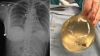

胸部を撃たれた女性、シリコン埋め込みのおかげで命拾い カナダ |